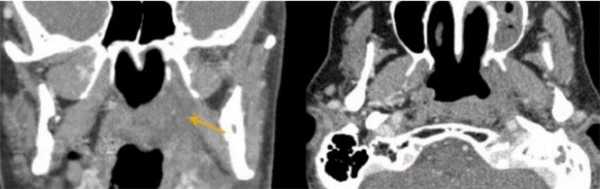

На КТ или рентгенографии определяется - дополнительное опухолевое образование в полости носа, или в одной из придаточных пазух носа, при второй стадии возможна деструкция участка костной ткани.

На КТ или рентгенографии определяется - дополнительное опухолевое образование, занимающее полость носа, распространяющееся на медиальную стенку или нижнюю стенку орбиты, верхнечелюстную пазуху, небо или решетчатую пластинку.

На КТ или рентгенографии определяется дополнительное опухолевое образование, занимающее полость носа распространяющееся на любую из следующих структур: на передние отделы орбиты, кожу носа или щеки, крыловидные пластинки основной кости, лобную или основную пазухи, минимальное прорастание в переднюю черепную ямку, верхушку глазницы, твердую мозговую оболочку, мозг, среднюю черепную ямку, черепные нервы, кроме V2.